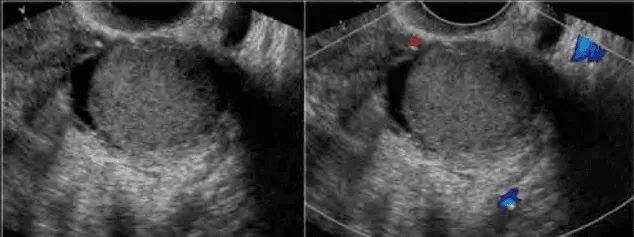

Phần tiêu đề “Cận lâm sàng”Hình ảnh “Nang lạc tuyến nội mạc tử cung ở buồng trứng”.

Siêu âm thang xám: Nang đơn/multiple phản âm kém đều, giới hạn rõ, không chồi/vách, không tăng dòng mạch. IOTA M-rules âm tính. Siêu âm đủ để chẩn đoán; MRI chỉ khi nghi ngờ lạc nội mạc sâu hay đau dữ dội.